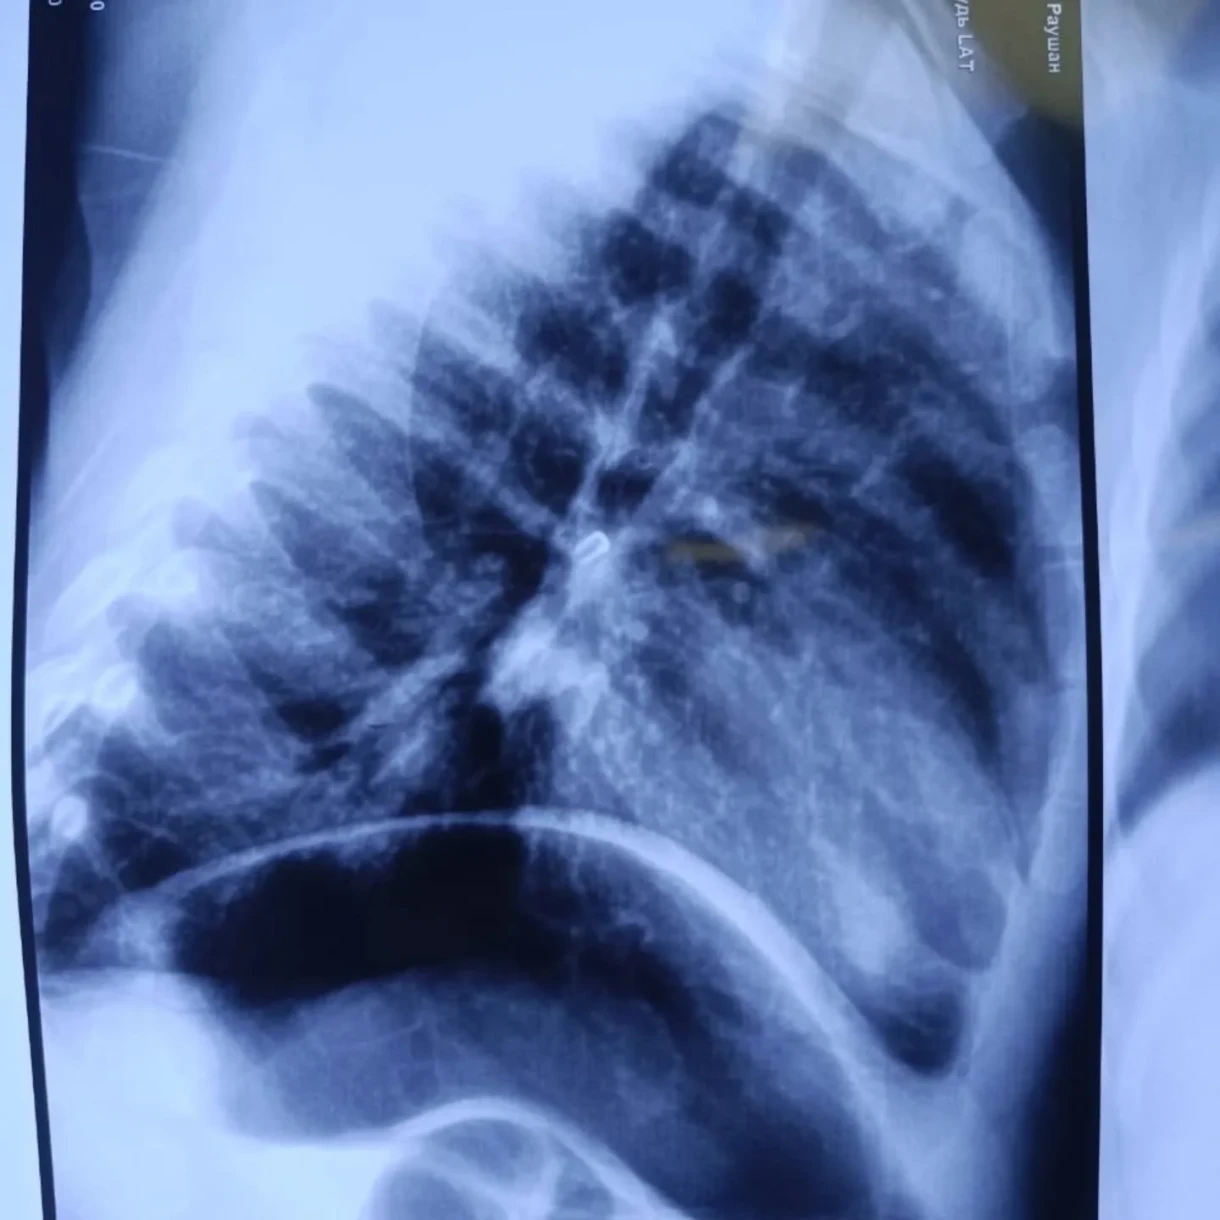

Upon admission, the child's condition was assessed as severe due to respiratory failure. An X-ray revealed the presence of a foreign body in the right main bronchus.

Doctors performed rigid bronchoscopy under general anesthesia and successfully extracted the foreign object, which turned out to be a small bead.